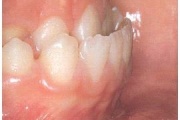

) Röntgenülesvõte. Ülemise esimese jäävmolaari lõikumine on takistatud 2. piimamolaari tõttu

Esimese jäävmolaari ektoopiline lõikumine